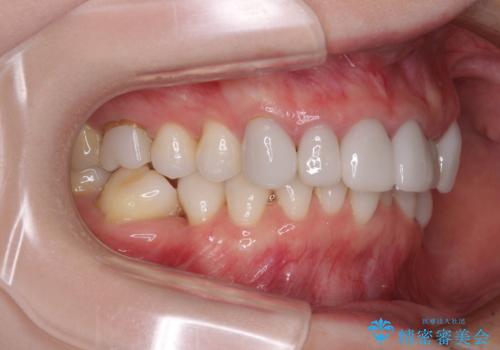

- 全体的なデコボコと、奥歯の欠損を放置した結果倒れ込んだ奥歯などを気にして来院された患者様です。

ワイヤー矯正の方が理想的な仕上がりとできる状態でしたが、上顎前歯にクラウンが装着されているため、インビザラインにて矯正治療を行うこととしました。

インビザラインのみで対応できないときにはワイヤー矯正を併用することとし、矯正治療後にはオールセラミッククラウンによる補綴治療を行うこととしました。

矯正治療自体はインビザラインで満足のいく仕上がりとなりました。

前歯は根管治療が必要となり、元々舌側に入り込んでいた左上2番目の歯は歯周外科処置により歯肉ラインを整えることとしました。

欠損部位は傾斜歯軸を起き上がらせることができたため、オールセラミッククブリッジにて補綴治療を行いました。

全顎的に満足のいく仕上がりとなりました。